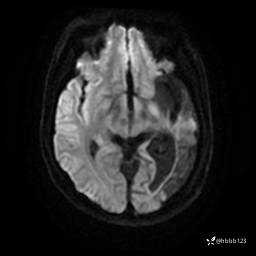

DWI: